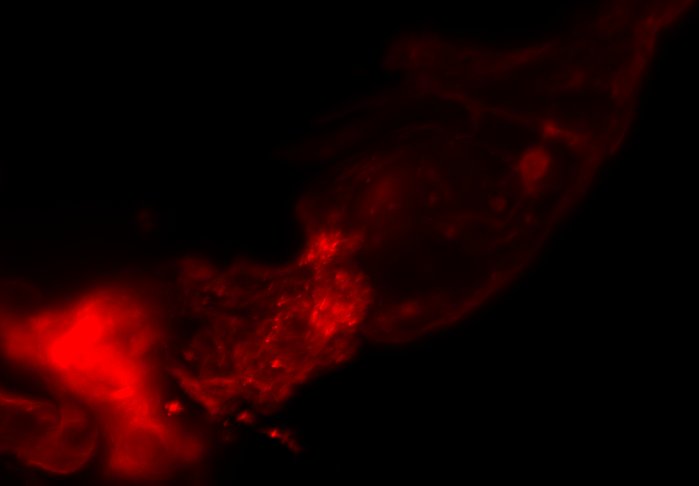

The combination of prospective optical gating for real-time phase matching and prospective optical gating for long-term phase locking allow us to capture in phase images over extended periods of times. Figure 4 demonstrates this phase locking over 18+ hours across a key developmental phase - heart looping.

We have previously shown the use of prospective optical gating with SPIM for the capture of 3D fluorescence data of the living, beating zebrafish heart. However, until now it was not possible to maintain synchronisation over timescales of an hour or more, due to changes in the appearance of the heart. Here we have demonstrated the successful application of combining prospective and retrospective optical gating techniques in order to update the reference heartbeat and phase lock between old and new references.

We have described how a combination of drift correction, inter-frame correlation and least squares regression can be used to accurately and robustly update the reference heartbeat and target frame. We have shown that this allows for phase locked imaging over developmental time scales. In particular we have demonstrated the ability to maintain synchronisation over 18+ hours around the heart looping stage of cardiac development in zebrafish.